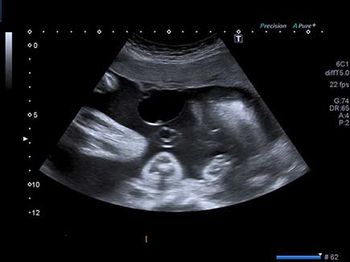

Challenge your diagnostic skills: Anything unusual about this fetal head?